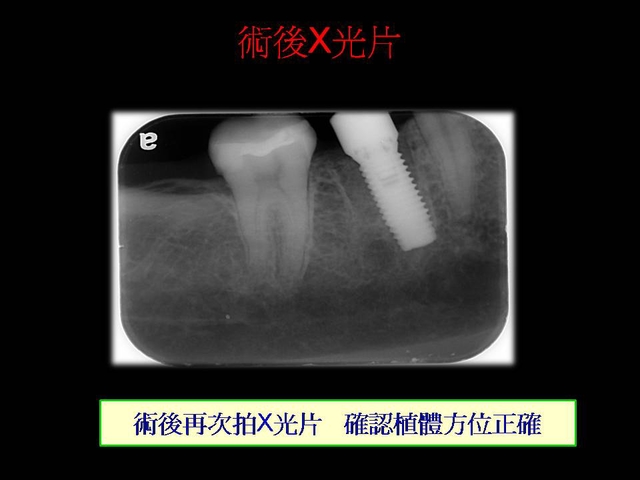

微創植牙介紹--pic介紹